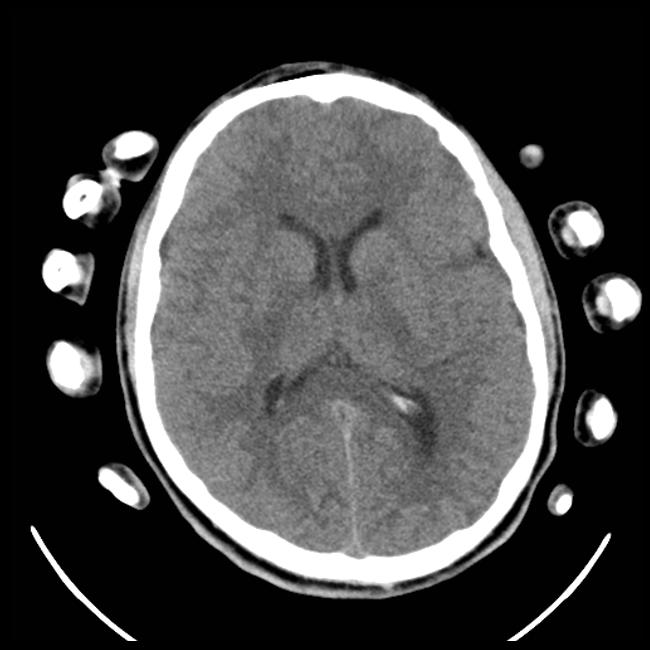

Clinician relevance annotations. App. D.4.2 provides a breakdown of clinician-annotated reasoning traces, revealing that the model mostly generates contents highly relevant to the diagnosis, with minimal output judged as irrelevant. We observe that the model often correctly recalls relevant clinical knowledge, which help guide the model by providing associative context. For example, in Fig  4(a), the model correctly recalls different signs of hemorrhage on CT, such as darker or whiter tissues, and relates this context to specific parts of the image to make a correct prediction. In Fig. 4(c), the model correctly identifies the presence of a pacemaker, indicating a support device, but subsequently concludes that there are no additional abnormalities, ultimately leading it to predict “No finding”. This suggests that while the model’s final predictions may be incorrect, its intermediate reasoning often reflects clinically relevant patterns.

Refer to caption

Figure 4: Model outputs annotated by clinical experts. QoQ-Med correctly reasons from modality-specific clinical knowledge, generates bounding boxes, and outputs the correct predictions in most instances except (c). (e) demonstrates the model’s ability to synthesize multimodal inputs with reasoning. The bounding boxes correctly highlight the salient regions related to the reasoning steps when one is present.

Bounding box quality. Fig. 3(b) demonstrates that the model identifies bounding boxes correlated with the ground truth annotations, with the IoU exceeding the best open source models while reaching a similar performance as the closed-source reasoning model o4-mini. From Fig. 4, we also see that the outputs by the model are sufficiently aligned with the reasoning process, allowing the clinicians to confirm the model’s predictions while cross-referencing the source image.